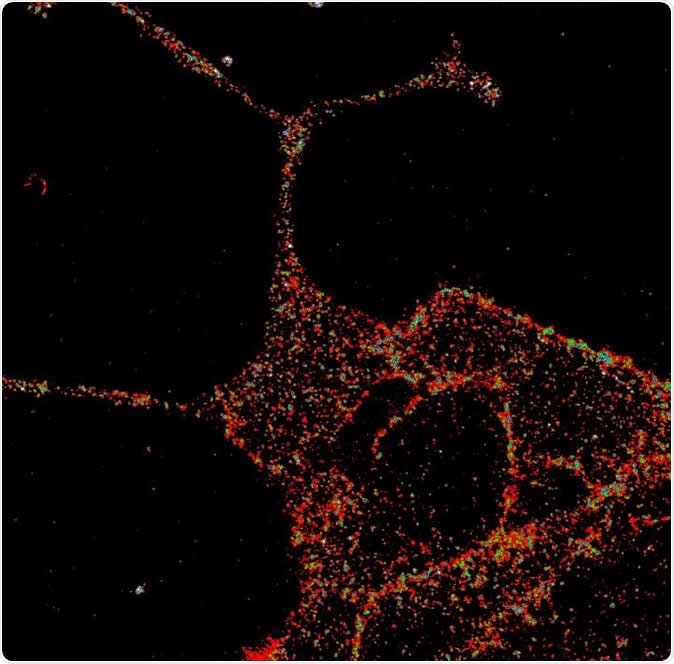

GLP1R visualized in insulin-secreting beta cells at super-resolution. Image Credit: University of Birmingham

They used several different methods of visualization, such as creating marker compounds in the form of fluorescent probes, immunostaining, super-resolution microscopy and the examination of the protein in live mice. Their probes were used to label the receptor which helped them locate it precisely inside the living mouse cell, as well as to understand how it responds to signaling chemicals. Super-resolution microscopy allows imaging at resolutions below the limit of wave diffraction. This makes it possible to study biological structures at resolutions comparable to the size of individual molecules. As a result, these are the preferred methods in visualizing proteins and the way they are organized within living cells.